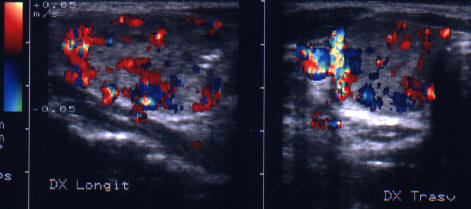

Acelasi pacient. La doppler color, vascularizatie bogata, difuza in toata

glanda

Artera tiroidiana superioara stg.

Artera tiroidiana superioara dreapta.

Acelasi

pacient. La doppler color, vascularizatie bogata, difuza in toata glanda